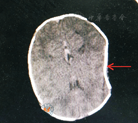

孕妇31岁,孕1产0,因"血压升高2月余",间断下腹痛5 h余,于2018年1月9日入住河北医科大学第二医院产科。患者平素月经规律,末次月经2017年4月13日,预产期2018年1月20日。2个多月前于当地医院产前检查发现血压升高,为140/90 mmHg(1 mmHg=0.133 kPa),伴双下肢水肿,未予治疗;后多次监测血压为160/110 mmHg,于2017年12月3日至10日住院治疗,给予解痉、降压、促胎肺成熟等综合治疗,病情好转出院。入院查体:血压155/100 mmHg,无胸闷气短不适,心肺未见明显异常,双下肢水肿(+)。产科检查情况:宫高31 cm,腹围107 cm,胎方位为枕左前,胎心音142次/min,可触及宫缩,子宫张力不大。出口横径8.5 cm,耻骨弓90 °。阴道检查:阴道通畅,宫颈软,宫口开大2 cm,头先露坐骨棘上3 cm,未扪及海绵状及条索状组织,骶尾关节活动,双侧坐骨棘平,骶凹形态好。12月9日查血常规,血红蛋白为81 g/L。入院诊断为:(1)孕1产0孕38+3周,枕左前位,临产;(2)重度子痫前期;(3)妊娠合并贫血。入院后急行超声检查,提示(1)宫内孕单活胎,枕左前位;(2)脐带绕颈一周;(3)胎盘下缘胎盘实质内靠近胎盘宫壁间低回声区待诊(胎盘早剥?);(4)胎儿超声孕周与临床孕周不相符,待诊。补充诊断:胎盘早剥。向患者及家属交代病情后行急症子宫下段剖宫产术。术中所见:清亮腹水约400 ml。羊水I°粪染,量约500 ml,以枕左前位娩一男婴,脐带绕颈3周,断脐后松解脐带,清理呼吸道。新生儿头颅左侧顶骨可见颅骨凹陷,范围约1.5 cm×2 cm,向内凹陷深约1 cm,凹陷处表面皮肤未见异常,无肿胀,无皮肤破损,余外观未见明显异常。新生儿出生体重2750 g,Apgar评分1、5和10 min分别为9分、10分、10分。子宫收缩好,胎盘胎膜完整。胎盘母面近胎盘边缘见一6 cm×5 cm大小压迹,位于脐带插入部,胎盘边缘可见大小约6 cm×3 cm×2 cm陈旧性血块,色灰黄,脐带长60 cm,边缘附着,无扭转。新生儿查体:足月儿外貌,前囟平坦,左侧颅骨可见一范围约1.5 cm×2 cm颅骨凹陷,深约1 cm;双肺呼吸音清,未闻及干湿性啰音;心律齐,心音有力,各瓣膜听诊区未闻及杂音;腹软,脐带无渗血及渗液;四肢活动自如,肌张力不高。联系新生儿科及神经外科医师会诊,新生儿医师嘱积极喂养,监测血糖。神经外科医师查体:囟门张力不高,建议密切观察,保守治疗,若长时间颅骨凹陷无缓解,建议门诊就诊。新生儿出生后第2天,监测经皮胆红素值增高、皮肤黄染,转入新生儿科,测定经皮胆红素:136.8 μmol/L,C-反应蛋白:10.2 mg/L,初步诊断为:(1)新生儿黄疸;(2)新生儿感染;(3)左侧颅骨凹陷。头颅CT检查示:两侧额顶叶白质密度减低,CT值为10~14 HU;脑干形态正常,未见变形、受压;脑室系统未见扩大、变形,脑室内无异常密度,脑沟、脑裂及所见脑池无变形与变窄,中线结构居中;左侧顶骨向内凹陷,骨质欠连续(图1),建议进一步磁共振成像检查。给予光疗、抗感染治疗及维生素K1预防出血等治疗,患者及家属拒绝MRI及应用脑神经营养药物,新生儿共计住院5 d,病情好转随母出院。患者术后第5天出院,出院时无头晕、心慌不适,子宫复旧好,腹部伤口无红肿及渗液,阴道少量血性恶露,无异味。产妇出院诊断:(1)重度子痫前期;(2)胎盘早剥;(3)妊娠合并贫血;(4)宫内孕38+3周第一胎,已分娩;(5)脐带缠绕。新生儿出院诊断:(1)新生儿黄疸;(2)新生儿感染;(3)左侧颅骨凹陷。新生儿出院后定期随访,无任何临床症状,未行任何处理,生后4个月后颅骨凹陷区域恢复正常。